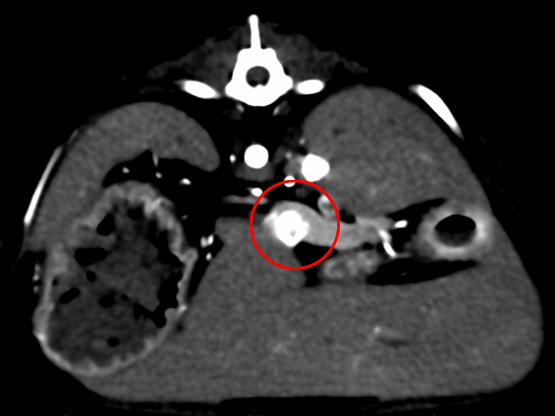

症状は特に見られなかったものの、血液検査で血糖値が低いことがわかりました。また、その時に測定したインスリンの値が高くなっていたため、膵臓に問題があるのではないかと考えました。 超音波検査を行いましたが、膵臓の位置の関係で腫瘤(しゅりゅう:できもの)をはっきり確認することが難しかったため、CT検査を実施したところ、膵臓の一部に腫瘤が見つかりました。 この結果から「インスリノーマ」という膵臓の腫瘍が強く疑われたため、腹腔鏡(ふくくうきょう)という小さな傷で体への負担が少ない手術で、腫瘤の摘出を行いました。 手術後の経過はとても良好で、術後3日で元気に退院されました。

術前のCT検査 CT検査にて腫瘤の位置、転移の有無を確認